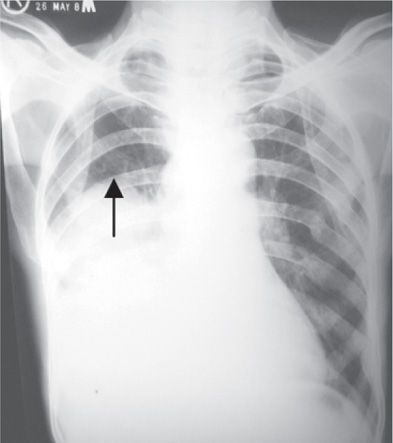

Hepatomegaly, also known as an enlarged liver, means your liver is swollen beyond its usual size Learn more about the causes, symptoms, riskEnlarged liver Xray of the chest of a 55 year old patient with an enlarged liver (hepatomegaly) The liver itself cannot be seen, but the disorder has been revealed by the raised diaphragm (white, lower left) An enlarged liver is usually a symptom of an underlying cause, such as cancer, high blood pressure (hypertension) or infectionSafeline Xrays guide är en referens för alla som är involverade i säkerhetshantering av livsmedel och läkemedel I guiden förklaras hur tillverkare kan utveckla ett effektivt program för röntgeninspektion för att hitta föroreningar och erbjuda konstant kvalitet och produktpresentation

A Chest X Ray Hepatomegaly With Dilated Small Bowel Loops And Few Download Scientific Diagram

From the case Hepatosplenomegaly Xray Loading Stack 0 images remaining Xray Scroll Stack Scroll Stack Frontal The inferior aspects of both the liver and spleen are well illustrated and lie at the level of the iliac crest The heart size is considered too large when the CTR is > 50% on a PA chest xray A CTR of > 50% has a sensitivity of 50% for CHF and a specificity of 7580% An increase in left ventricular volume of at least 66% is necessary before it is noticeable on a chest xray On the left a patient with CHFDistended Neck Veins & Hepatomegaly & XRay Abnormal Symptom Checker Possible causes include Cor Pulmonale Check the full list of possible causes and conditions now!